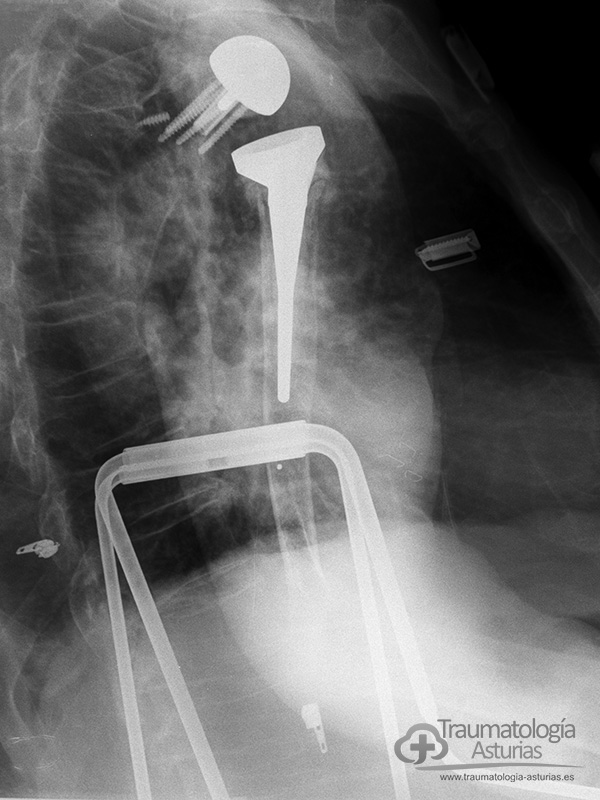

Las cirugías protésicas repetidas en el hombro procovan un déficit del tejido óseo, sobre todo glenoideo, que requiere el uso de injertos óseos y el uso de técnicas quirúrgicas originales para dar estabilidad primaria a la articulación como en este caso un tornillo guia canulado a la fosa supraespinosa y el tope óseo acromio-coracoideo apoyado en placa de osteosíntesis